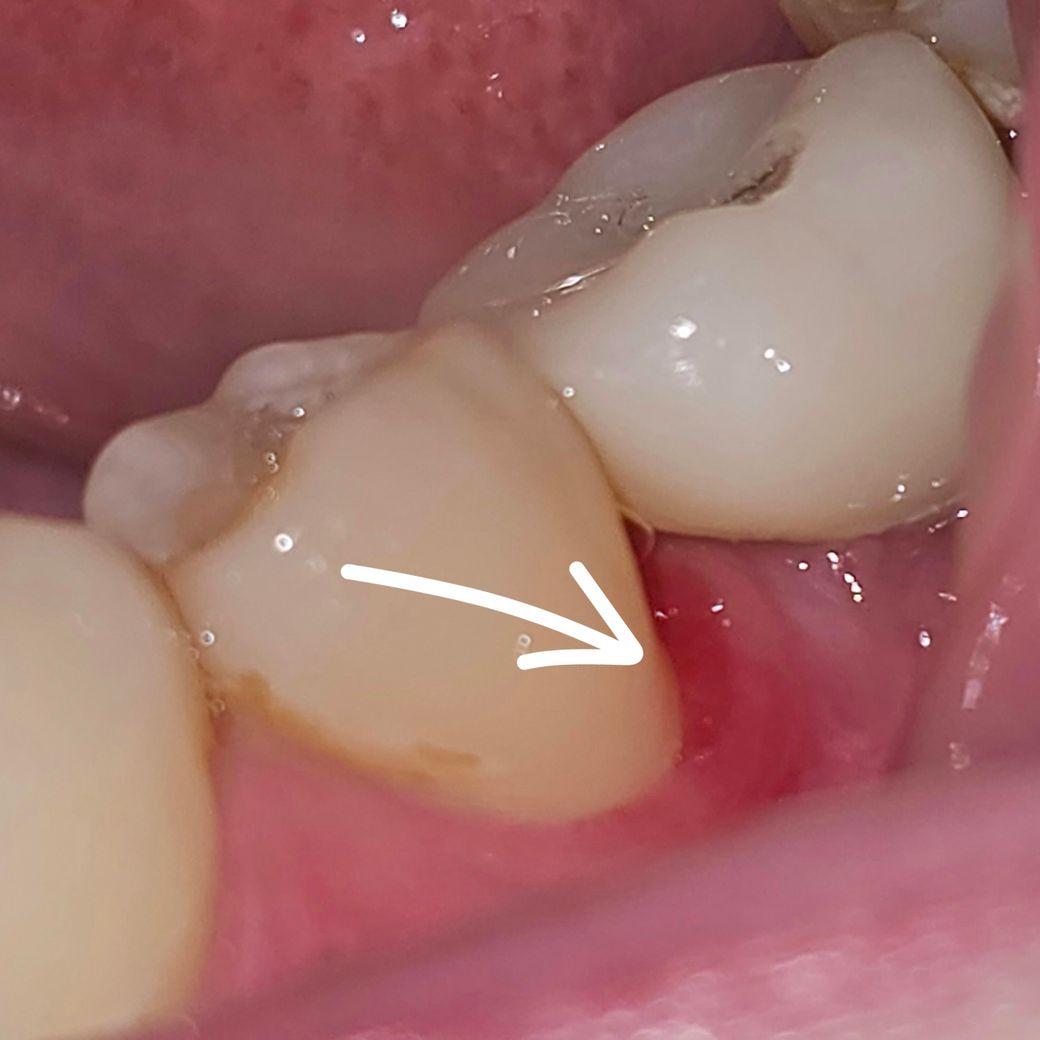

<발견첫날>

옆 치아 잇몸이 빨갛게? 상처처럼 생기며 피가 났거든요.

약간 궤양? 같기도하고 생긴게 상처난 피부가 염증으로 물러진 것 처럼 생겼습니다.

닦으면 피가 뭍어 나옵니다.